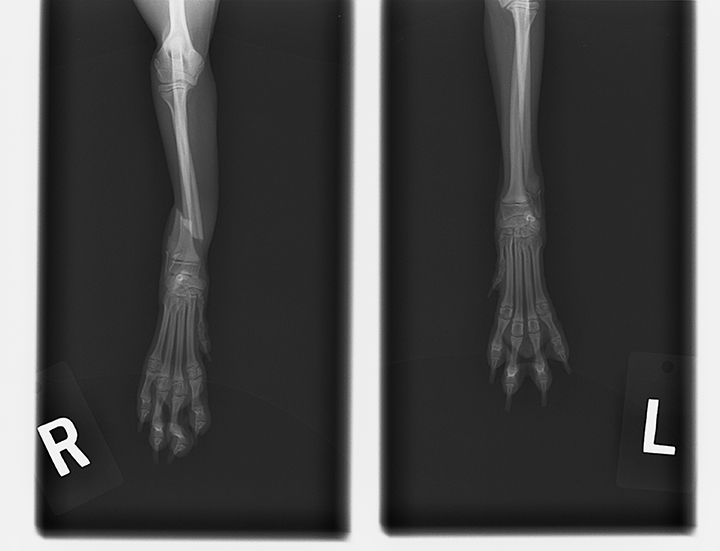

問題なのは右手の骨が2本共に斜めに折れてしまっていることです。細いほうの骨のみならギプスのみでさほど問題ではないようですが、太いほうが折れてしまうとズレたまま繋がってしまう恐れもあるそうで。

骨が細いので一度切開して骨の位置を合わせプレートを当て、そのプレートでずれないようにネジを打ち込み固定する方法がベストだそうです。骨折から2日経過しているわけで再度レントゲンを撮ってもらったところ、やはり折れた骨同士の位置が完全にずれてしまってました。